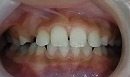

治療前の写真では、前歯が一本だけ咬み合わせが上下逆になっています。

治療後は、前歯の咬み合わせが改善しています。

期間は、1年6カ月で治療方法は独自の方法です。

この症例は、前歯という特に神経が敏感な場所でもある為、

早期に治療してあげたい症例です。